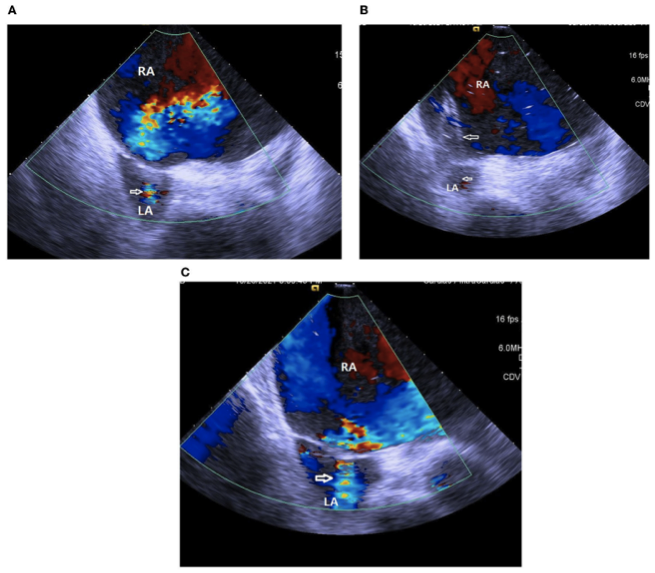

一年半后,患者因更换PICC再次入院,并再次接受心导管检查。ICE证实存在由先前的BAS创建的心房分流(图2A)。血流动力学数据显示平均RA压力为5 mmHg,LA压力为2 mmHg,全身CO为3.3 L/min,OD为403 mL/min。这些结果支持持续的血流动力学改善。使用8 mm球囊进行第二次BAS(图2B)。ICE显示在第二次BAS后从右向左分流增加(图2C)。第二次BAS导管插入术后测量显示平均RA压力为3 mmHg,LA压力为3 mmHg,全身CO 3.4 L/min,OD为420 cc/min。患者因稳定的功能性II症状出院。

图2. (A)ICE证实了先前球囊房间隔造口术造成的房间隔分流(白色箭头)。(B)ICE显示在第二次球囊房间隔造口术中一个8 mm的球囊(白色箭头)膨胀。(C)第二次球囊房间隔造口术后ICE显示从右向左分流增加(白色箭头)